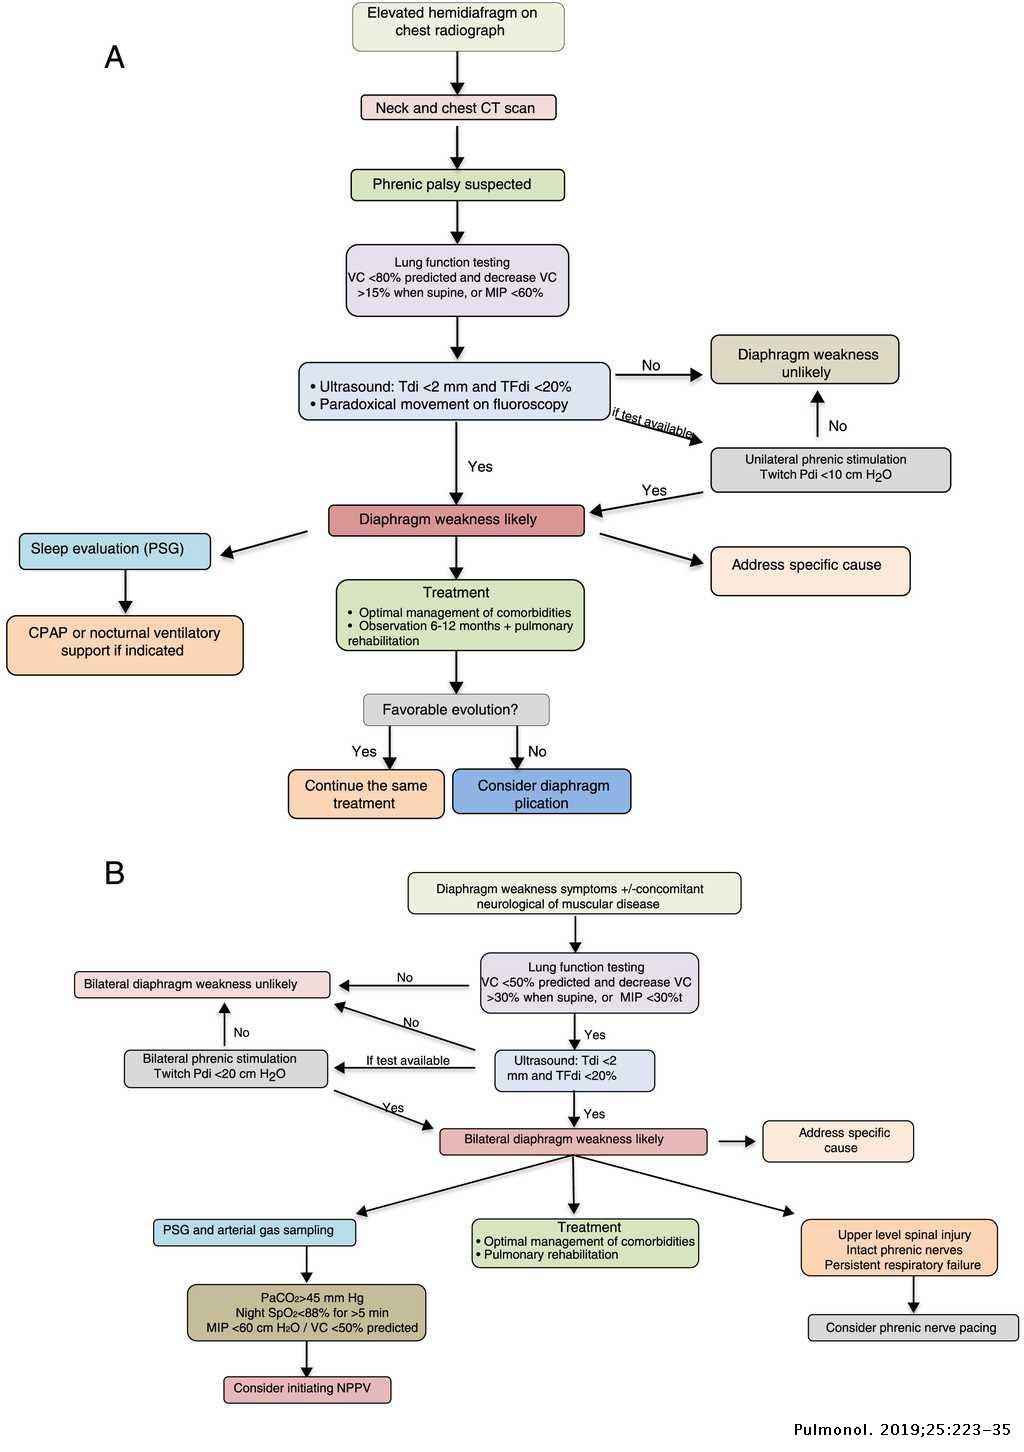

Smoking is the primary cause of emphysema which makes it a preventable illness. Diaphragm weakness due to medical intervention most commonly occurs as a result of physical trauma to the phrenic nerves or diaphragm muscle. Surgical treatment is an option for more advanced cases or if breathing becomes so impacted daily life is affected.

You may not need any treatment. Depending on the severity of injury to the diaphragm some doctors recommend non-surgical options to treat the breathing issues associated with diaphragm weakness and paralysis.

The rise in intraabdominal pressure further increases intrathoracic and lung volume by pushing the lower rib cage outward. In severe cases when there is no simple treatment that can relieve dyspnea your doctor may prescribe morphine. Diaphragmatic dysfunction caused by transverse myelitis or leukemic infiltration of the cervical spinal cord in a patient with leukemia and shortness of breath. Diaphragmatic plication a surgical procedure that pulls the diaphragm down by introducing a repeated series of continuous sutures across the diaphragm and pulling the muscle taut. A bedside fan or open window with a breeze are also simple but very effective treatments to lessen dyspnea. Depending on the severity of injury to the diaphragm some doctors recommend non-surgical options to treat the breathing issues associated with diaphragm weakness and paralysis. P E Pulmonary embolism.